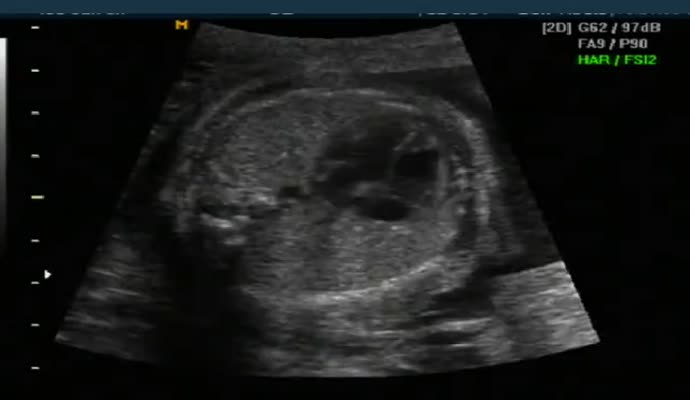

아래는 초음파 영상이기는 하지만 그렇게 올려진 영상 샘플입니다.

ob_usg_normal.mp4.jpg (17.74 KB, 다운수: 484)

ob_usg_normal.mp4

5.07 MB, 다운수: 872